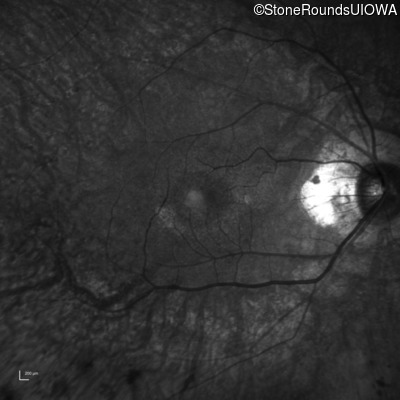

Infrared Fundus Photograph - Right - 20/25 -2 sc

Exemplar